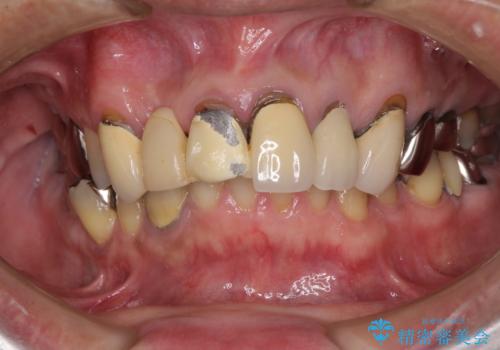

- 前歯のブリッジのセラミックが欠けてしまい、作り直したいとのことで来院された患者様です。

犬歯はブリッジの中で虫歯が進行していたため、根管治療からやり直しをした後、オールセラミックブリッジにて補綴することとしました。